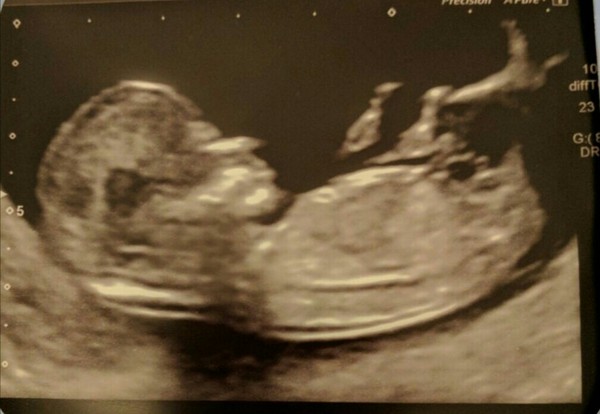

Hope everyone is doing well. I had my 12 week scan last Friday and all seemed good, so feeling really relieved. Can't believe how like a baby the baby looks! Am due 1st Nov.

Lovely scan msbranwen